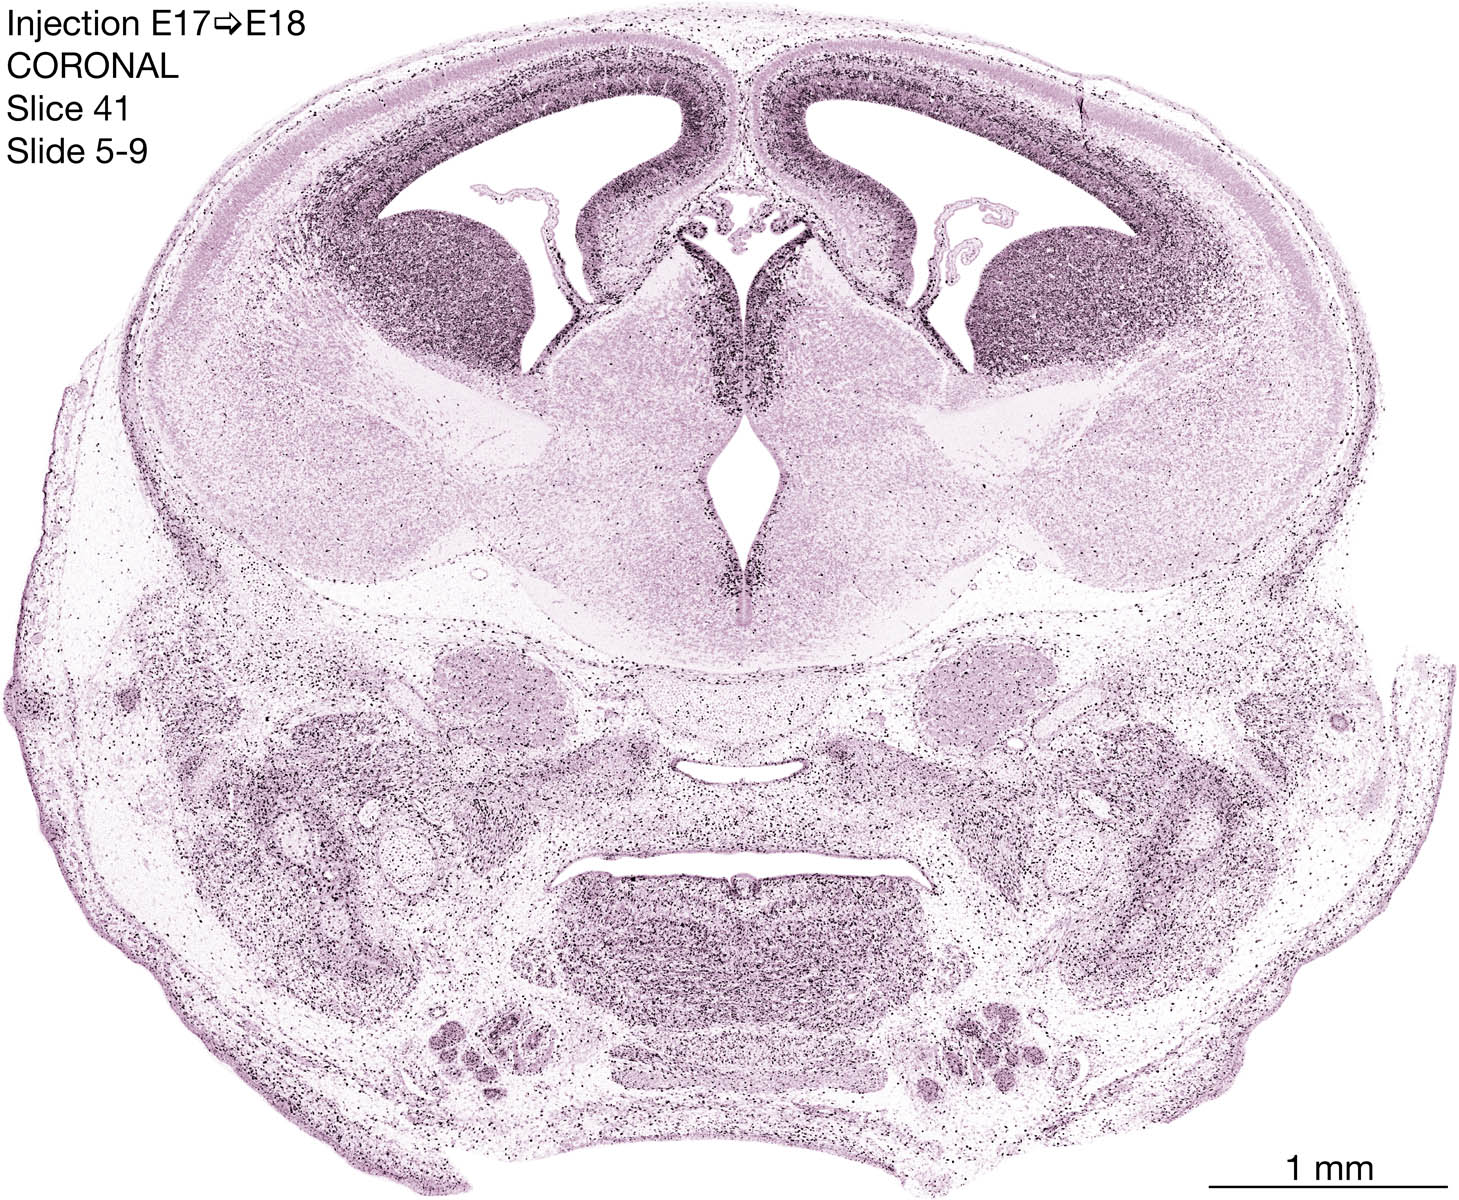

E17 to E18 Survival Archived Images-Coronal

The following images are from a coronally-sectioned head of an E18 rat embryo exposed to tritiated thymidine on E17–24 hr survival.  Note the heavily-labeled cells just outside the germinal zones are now mainly in the diencephalon and forebrain.  These are postmitotic young neurons generated ON E17.  Note that the banded labeling is prominent outside the neocortical neuroepithelium.  Many of the germinal zones in the brainstem have become transformed into the primitive ependyma, and the entire brainstem is becoming more mature; the only primitive area is the cerebellum, where the external germinal layer is now more prominent.